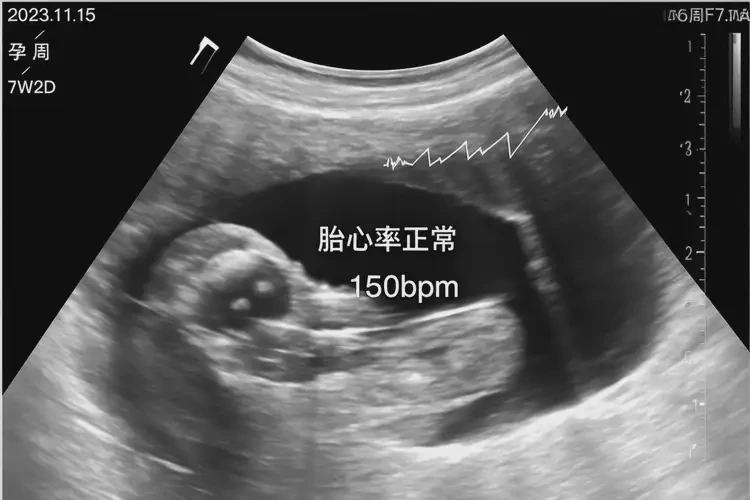

胎心率178次/分鐘在孕7周屬于正常范圍

孕7周時,胎兒的胎心率在120-180次/分鐘之間都被認為是正常的。胎心率178次/分鐘并不意味著胎兒有危險,通常情況下是可以保住的。胎心率的監(jiān)測只是評估胎兒健康狀況的一個方面,還需要結(jié)合其他因素來綜合判斷。

• 孕早期(6-10周):胎心率通常在120-180次/分鐘之間。

孕7周胎心率178還能保住嗎(圖1)